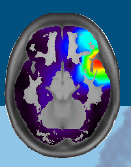

(9) Infinitivkonstruktionen kritisch - am Beispiel der Infinitivkonstruktionen im Rahmen des Agrammatismus bei Broca-Aphasie

Referentin: Judith Zink (14.11. / 9,41)

Schecker, Michael (2005): Der Infinitiv als default-Form bei aphasischem Agrammatismus (zusammen mit G. Kohls). In: J.-F. Marillier J.-F. / Rozier C. (Hrsg): Der Infinitiv im Deutschen, Stauffenburg,  21 ff. (Eurogermanistik 22)